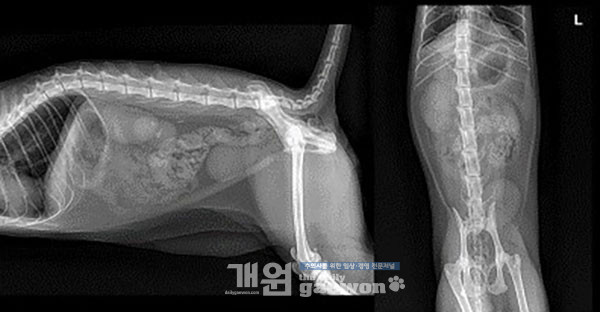

Renal margin은 contour되어 관찰되었고, corticomedullary definition은 다소 indistinct하게 관찰됩니다(그림 6). 이 증례에서는 두 개의 싱글 타입을 양쪽으로 장착하였습니다(그림 7).